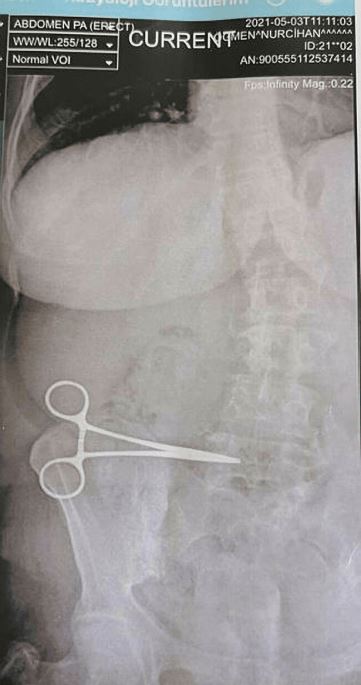

Shockingly, an x-ray of the woman’s abdomen showed that there was a pair of scissors left in her by the irresponsible surgeon.

woman discovers scissors in stomach that was left behind from previous surgeryImage via MYKMU.net

After the shocking discovery in her abdomen, the woman returned to the surgeon who removed the scissors during a two-hour operation.